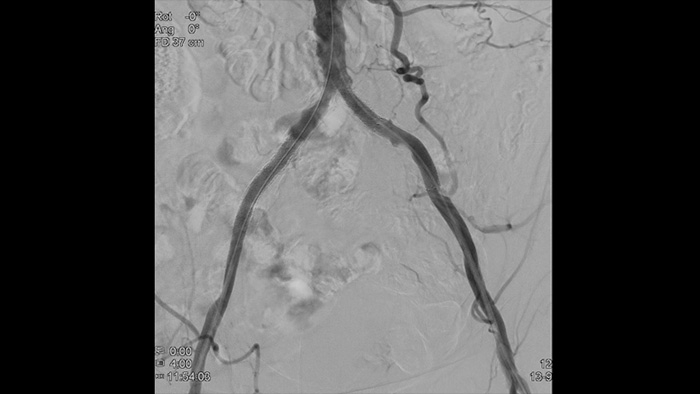

フィリップスのVascular suiteは、ワークフローオプション、専用のインターベンショナルツール、および幅広い高度な血管デバイスを提供して、手技の効率を改善し、大動脈疾患の患者の転帰を大きく改善します。これらは、治療の選択、支援、実施、結果の確証という手技の各ステップをサポートします。

Azurionの導入によってワークフローの改善が実現し、その結果として効率性の向上が実証されています。大動脈疾患の患者数が増え続けているなか、Azurionは、血管疾患治療チームが作業の効率性と一貫性を保ちながら、インターベンションにおいては患者と放射線被ばくの管理に集中できるように設計されたワークフローのイノベーションを数多く提供しています。